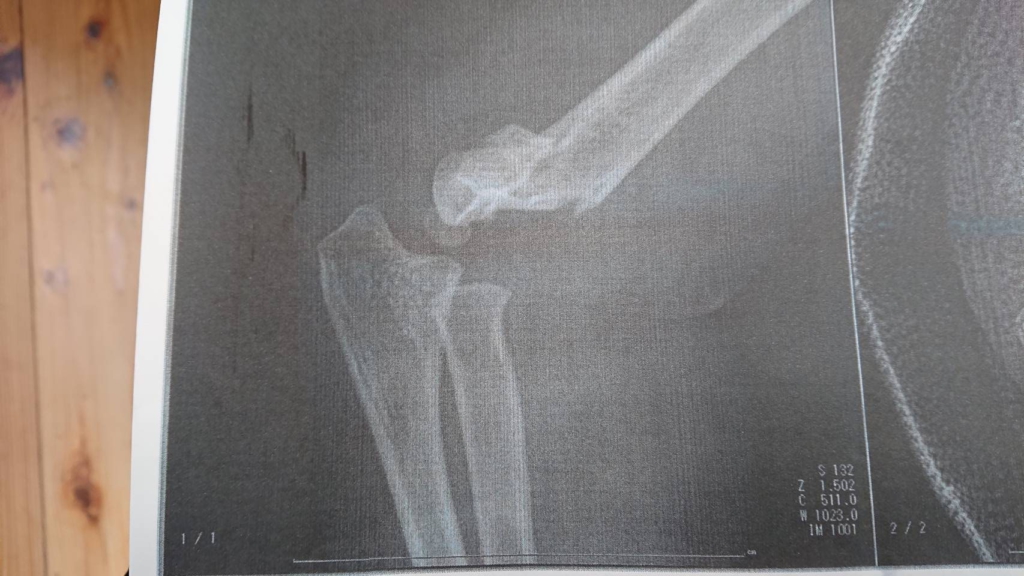

したがって、骨折や脱臼など急性外傷の来院率が高い。(期間中に来院した患者は保育園児、上腕骨顆上骨折の新鮮症例だった、木内先生からレントゲン情報をいただいた)